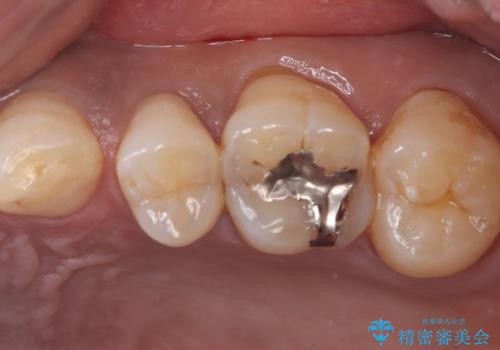

左上5番目の歯の側面に実質欠損を認め、隣の6番目の歯にも虫歯を認めたため両歯ともセラミックインレーでの治療となりました。

左上5番遠心に実質欠損を認め、さらに5番と6番の隣接面にもカリエスを認めました。6番の咬合面には、元々コンポジットレジン修復が施されており、劣化がみられたのでその部分も含め修復することとなりました。